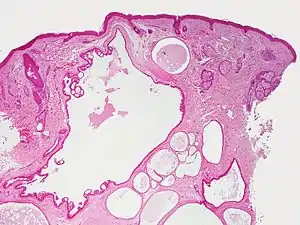

Hidrocystoma

Hidrocystoma (also known as cystadenoma,[1] a Moll's gland cyst,[1] and a sudoriferous cyst[1]) is an adenoma of the sweat glands.[2]:787

Hidrocystomas are cysts of sweat ducts, usually on the eyelids.[3]:664 They are not tumours (a similar-sounding lesion called hidroadenoma is a benign tumour).

Hidrocystomas usually arise from apocrine glands. They are also called Cysts of Moll or sudoriferous cysts. There may be a type of hidroadenoma that arises from eccrine glands, but these are uncommon.